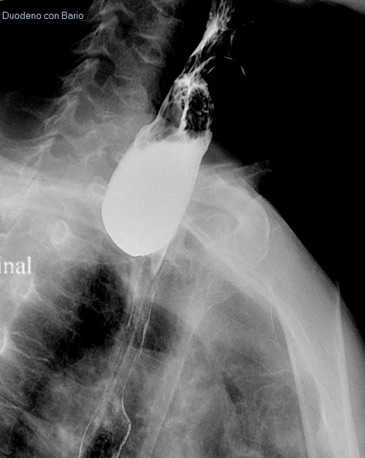

72 years-old male patient admitted to the hospital by failure breathing and loss of weight. Personal history of severe COPD. Presents dysphagia progressive severe of several months of evolution. The barium study shows a diverticulum of longitudinal diameter 8 cm. Gastroscopy shows the bottom of the diverticulum and removing the endoscope esophageal lumen appears to the right. Due to the high risk of anesthetic procedure took place without orotracheal intubation with sedation with midazolan and propofol managed by gastroenterologist.